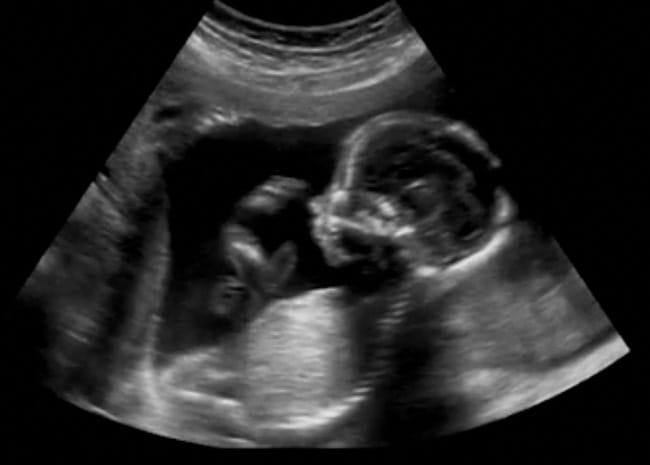

Janin sebenarnya sudah mulai dapat bergerak saat usianya menginjak 7–8 minggu. Pergerakan janin ini umumnya belum dapat dirasakan, tetapi sudah bisa terlihat ketika Bumil menjalani USG kehamilan. Namun, Bunda perlu mewaspadai gerakan janin yang tidak normal berikuti ini:

Bila sampai usia 24 minggu Bumil tidak juga merasakan gerakan pertama janin, sebaiknya konsultasikan kepada dokter. Dokter akan melakukan pemeriksaan USG untuk melihat pergerakan janin serta detak jantungnya.